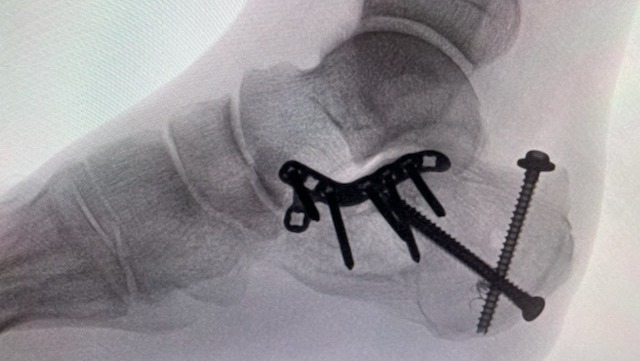

Reconstructive surgery on his shoulder and surgery to re-articulate his foot both required permanent implants. After weeks in the hospital recovering, doctors discovered blood clots in both legs and a previously missed fracture in his right tibia, meaning Kenn could no longer stand. During therapy sessions he'd actually been putting all his weight on a broken leg.